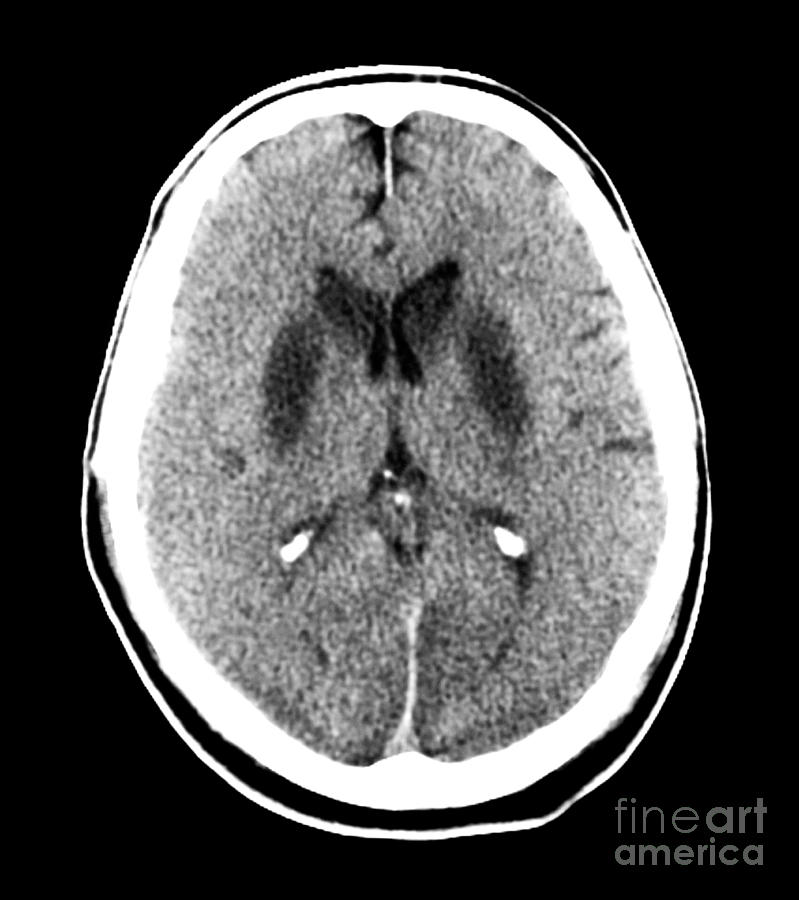

A meta-analysis of predicting outcome after arrest. The eyes still have it prior to 72hr. SSEP and status myoclonus remain strong indicators.